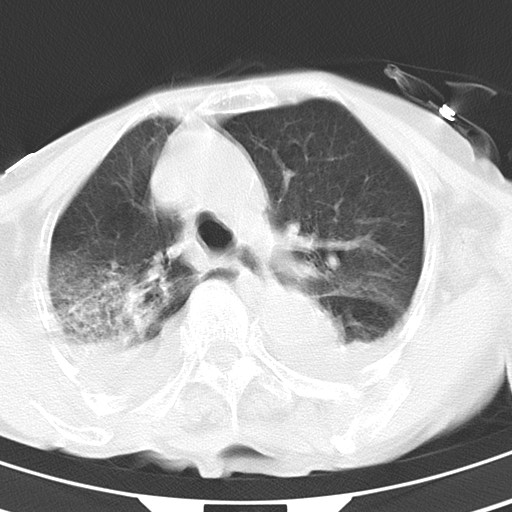

女,93岁,摔伤后检查。

右肺炎症,心功能不全伴双侧胸腔积液,右下肺膨胀不全,食管裂孔疝,冠脉钙化,心包少量积液,左侧肋骨骨折,请上传骨窗.

双肺感染合并双侧胸腔积液、胸膜增厚粘连,骨性胸廓未见明确骨折征。

右侧锁骨\\肩胛骨骨折、右侧湿肺,心功能不全伴双侧胸腔积液,右下肺膨胀不全,左膈破裂或食管裂孔疝,冠脉钙化,心包少量积液,请上传骨窗.

右肺炎症,心功能不全伴双侧胸腔积液,右下肺膨胀不全,食管裂孔疝,冠脉钙化,心包少量积液,左侧肋骨骨折,右肩甲骨粉碎性骨折。93岁,高寿哇!

右肺炎症,心功能不全伴双侧胸腔积液,右下肺膨胀不全,食管裂孔疝,冠脉钙化,心包少量积液,左侧肋骨骨折,右肩甲骨粉碎性骨折。